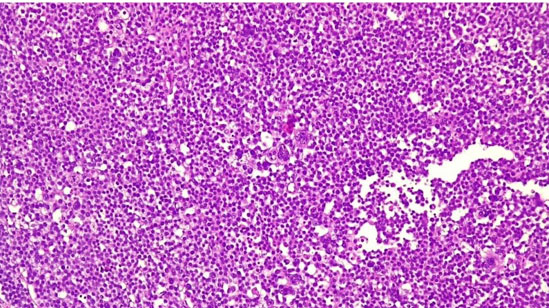

Grossly the tumor was well circumscribed with a nodular appearance, and a maximum diameter of 41 mm, on cut showed zones of fleshy, white to tan tissue, mucoid, and gelatinous change without paratesticular extension. Microscopically the tumor showed a polymorphous population of cells (Figure 2) that consists of three major types: a small, lymphocyte-like cell, an intermediate-sized cell, and giant cell, some of which were multinucleated. The borders between cells, in contrast with seminoma, were indistinct. No prominent lymphocyte infiltrates were found, neither was a GCNIS. No evidence of infiltration of rete testis or paratesticular structures was found. Most immunohistochemical markers of germ cell including OCT3/4 (Figure 3), CD30, Glypican-3, beta-hCG, and PLAP were negative as well as lymphoid markers (CD20, CD79a, Bcl-2, Bcl-6, c-Myc, MUM-1, and PAX-5). On the contrary CD 117 was focally positive. Based on immunohistochemistry as well as morphology the tumor was classified as a spermatocytic tumor.

Figure 2: Polymorphous populations of cells in spermatocytic tumor. Em-Eosin 10×.